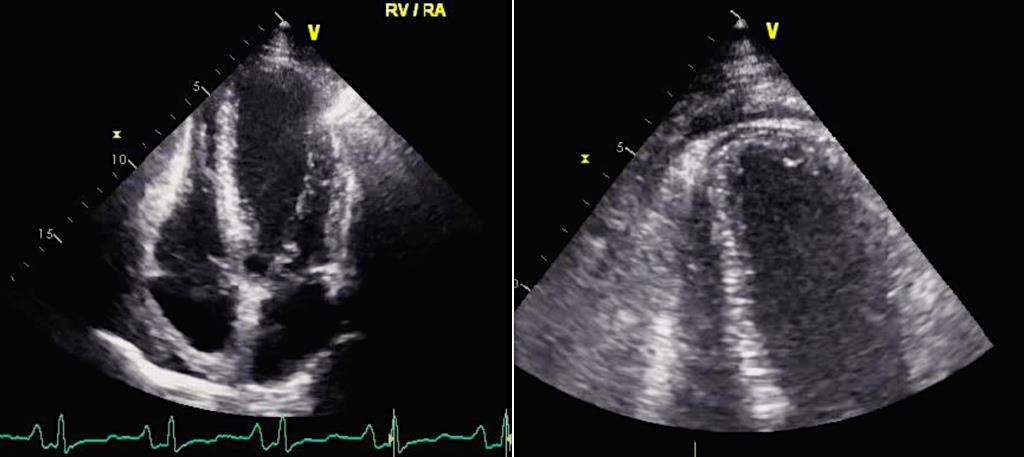

При нарастании выпота перикарда ЭхоКГ визуализация подтверждает формирование тампонады, что проявляется:

-

компрессией во время диастолы ПЖ, или его коллабированием в тяжелых случаях;

коллабированием правого предсердия (ПП) в систолу [142].

У пациентов с тампонадой сердца при дыхании могут выявляться значительные изменения размеров камер сердца. Так, при вдохе отмечается увеличение ПЖ с сопутствующим уменьшением размеров ЛЖ. Наоборот, во время выдоха ПЖ уменьшается в размерах с одновременным увеличением размеров ЛЖ.

Однако следует отметить, что в определенных условиях некоторые эхокардиографические особенности формирования тампонады сердца, такие как правожелудочковая компрессия, тяжелая легочная гипертензия и гипертрофия ПЖ могут отсутствовать (Приложение А3, рис. 9) [142].

Обычно при тампонаде сердца в разные фазы дыхания наблюдаются значительные изменения трансмитрального и транстрикуспидального потоков. Во время первого сокращения сердца после вдоха максимальная скорость трансмитрального пика E уменьшается более чем на 30%, в то время как во время первого сердечного сокращения после выдоха максимальная скорость транстрикуспидального пика E уменьшается более, чем на 60% [142, 143].